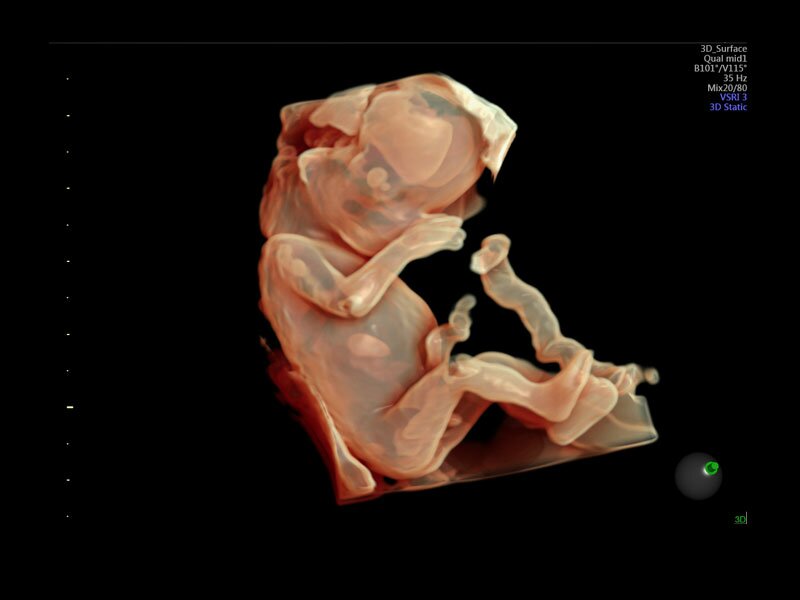

• Программа объемной визуализации плода классический HD-Live + расширенный пакет Hdlive Silhouette и Studio:

• HDlive Flow - перемещаемый источник света, совместимый с визуализацией кровотока в 3D

• HDlive Silhouette - режим "Силуэт" с подчеркиванием границ тканей и объектов, "объем в объеме"

• HDlive Flow Silhouette - режим "Силуэт" с выделением границ полостей сердца и сосудов, совместимый с визуализацией кровотока

• HDlive Studio - три независимых источника освещения с регулировкой интенсивности

• Автоматическое определение плода в режиме 3D (SonoRenderLive) – позволяет значительно экономить время и получать изображение конечностей и лица плода в режимах 3D без артефактов и помех – система автоматически определяет границы конечностей и лица плода и выстраивает объемное изображение

Объемное сканирование Voluson — 3D/4D вашей мечты

Объемное УЗИ на Voluson E10 — это не просто потрясающе красивая картинка, это ценный инструмент получения дополнительной информации при обследовании женщин.

Voluson E10 поддерживает инновационные технологии формирования изображений — HDlive Silhouette и HDlive Flow, которые позволяют увидеть мельчайшие детали. Алгоритм SonoRenderlive упрощает рабочий процесс и дает возможность реконструировать изображение поверхностей, определяя область перехода между тканью и жидкостью.

• HDlive

Инновационная технология визуализации HDlive обеспечивает получение реалистических изображений за счет эффекта объемного зрения, повышая достоверность клинической оценки. Теперь режим HDlive дополняют две новые функции:

• Технология HDlive Silhouette — задает разный уровень прозрачности, помогая выявлять контуры внутренних структур и точнее оценивать состояние плода в первом триместре.